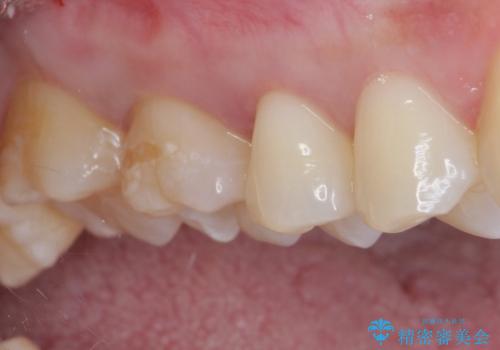

- 銀歯をセラミックにしたいとのことで来院された患者様です。

まず麻酔をして銀歯を外し、むし歯を除去し、形を整えて型取りします。

そして次の来院時、セラミックインレーを装着し、噛み合わせなどの調整を行います。

それを左右に分けて行いました。

インレーを装着するときは、唾液や血液による接着力の低下を避けるためにラバーダム防湿を行いました。

自然な色調で大変満足されました。